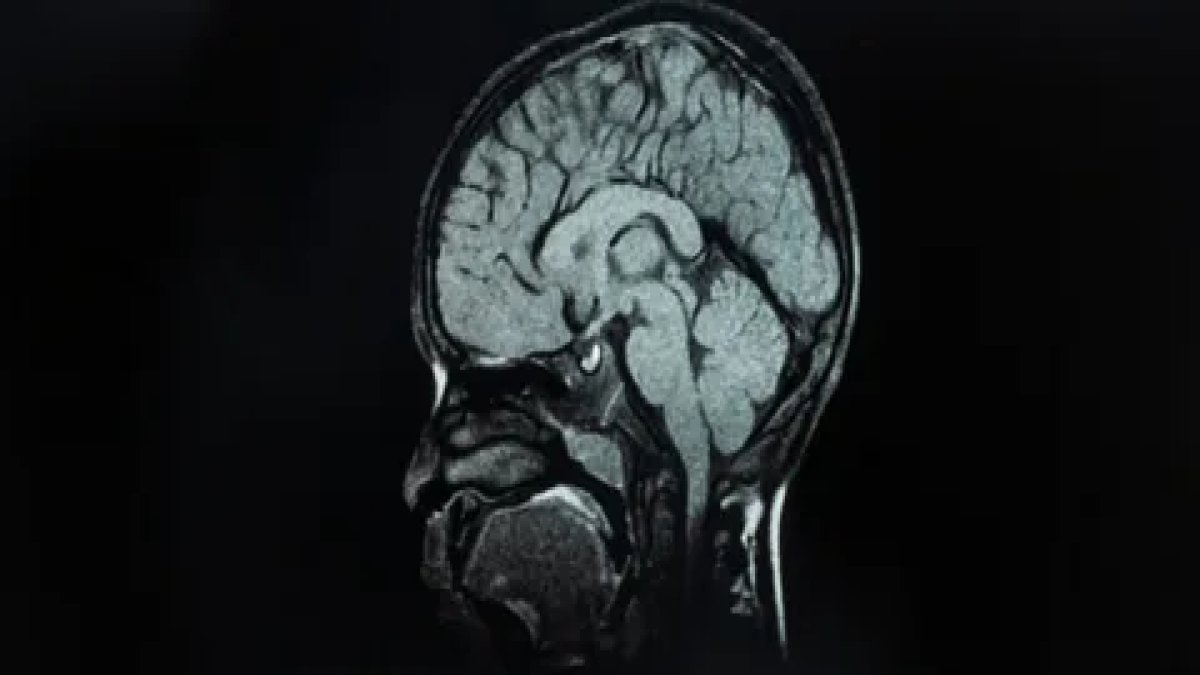

Epilepsiye birçok farklı neden yol açsa da vakaların yaklaşık yüzde 30’unun beyindeki yapısal bozukluklardan kaynaklandığı biliniyor. Ancak bu anormallikler, özellikle beynin kıvrımlarının derinliklerinde saklı olan çok küçük lezyonlar olduğunda, standart MR görüntülerinde çoğu zaman fark edilmiyor.

Melbourne Kraliyet Çocuk Hastanesi’nden pediatrik nörolog Emma Macdonald-Laurs liderliğindeki araştırma ekibi, çocuk beyin görüntüleri üzerinde bir yapay zekâ modeli eğiterek, “yaban mersini büyüklüğünde ya da daha küçük” lezyonları saptamayı başardı.

Araştırmada, kortikal displazi ve fokal epilepsi hastaları üzerinde testler gerçekleştirildi. Daha önce MR sonuçları “normal” raporlanan çocukların yüzde 80’inde aslında gizli lezyonların bulunduğu belirlendi.

Yapay zekâ aracı hem MR hem de PET taramalarını analiz ettiğinde, bir test grubunda yüzde 94, diğerinde yüzde 91 başarı oranı elde etti. İlk grupta yer alan 17 çocuktan 12’si, tespit edilen lezyonların çıkarılması için ameliyat edildi ve 11’inin artık nöbetsiz yaşadığı bildirildi.